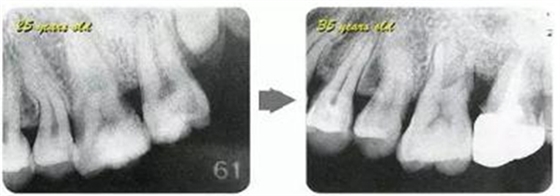

牙周病的發(fā)展因部位不同而發(fā)展程度不同的。10點(diǎn)后的狀態(tài)參考病例①和參考病例②的磨牙處的狀態(tài)相比較,思考下沒(méi)接受治療病情發(fā)展的特別性吧。

參考病例① 35歲女性

在左下第一磨牙在25歲時(shí)近中處可以看到垂直性的骨吸收,但35歲時(shí)吸收停止,原本沒(méi)有見(jiàn)到的遠(yuǎn)中處骨吸收的,現(xiàn)在卻吸收得很嚴(yán)重。

在右下處,原本有大量骨吸收的第一磨牙處的吸收卻變緩慢,原本沒(méi)有吸收的第二前磨牙卻出現(xiàn)了吸收。出現(xiàn)吸收的左上第一磨牙的遠(yuǎn)中處,吸收得越來(lái)越多了。

把10年間的變化做成表格。牙周病的發(fā)展根據(jù)各個(gè)人會(huì)不同,即使通一個(gè)人,不同牙齒,不同牙面發(fā)展的狀態(tài)也不同。